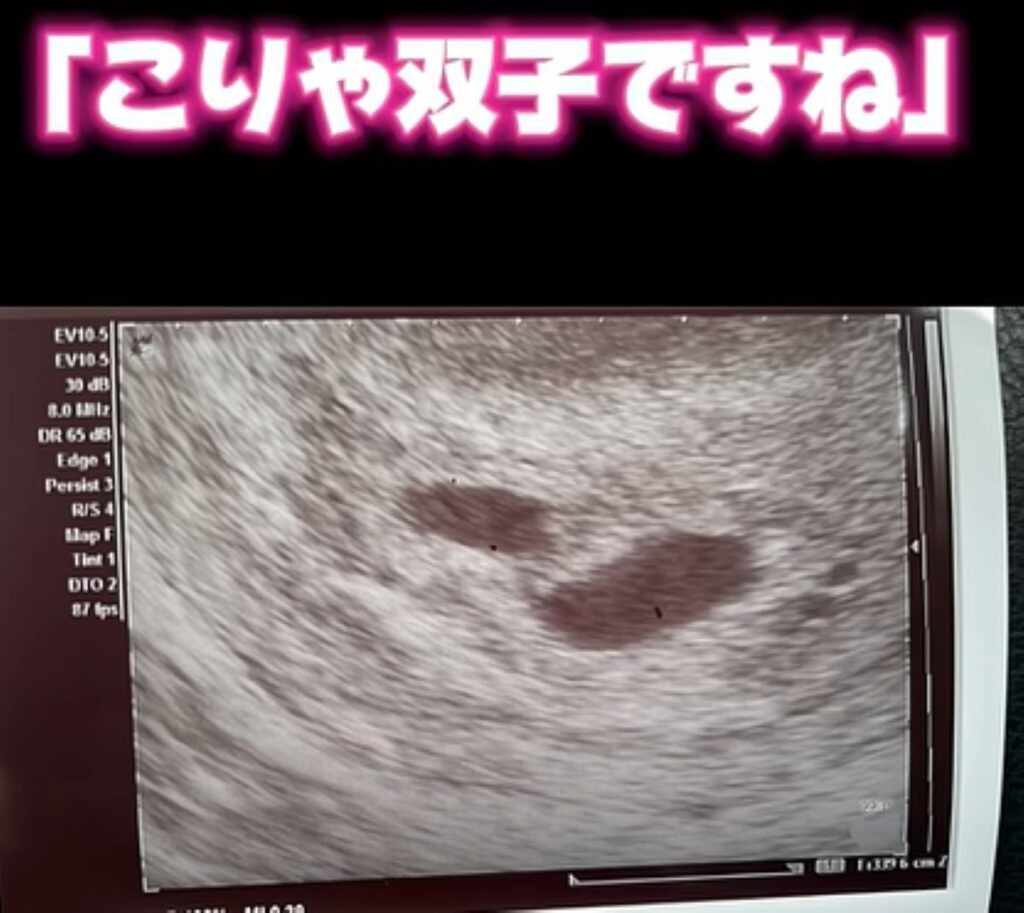

【実際の写真6枚】 エコーの様子